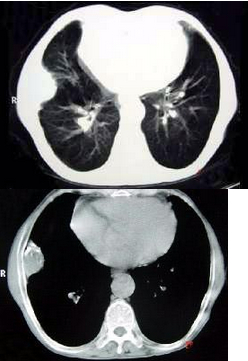

CT图像如下,最可能的诊断为()

A .右肺肺占位

B .右侧胸膜良性病变

C .肋骨病变侵犯胸壁

D .膈膨升

E .纵隔肿块